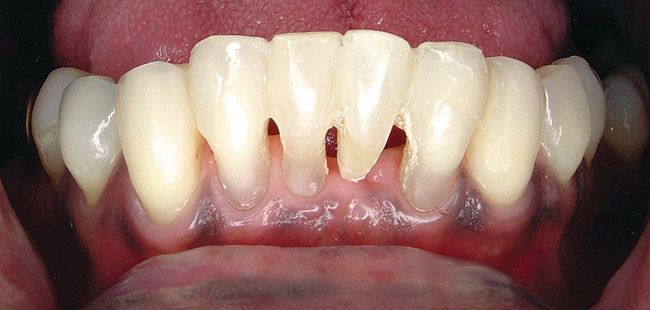

When fiber-reinforcing materials were introduced, the focus for their use was for periodontal splinting and stabilization resulting from tooth mobility.6,10,16,41-43 There is no doubt that splinting does reduce tooth mobility while the splint is in place.44 In the last decade, research supports the use of periodontal splinting as recommended therapy to stabilize those teeth to improve long-term prognosis.45-47 In a long-term clinical evaluation of splinting over a period of 48 to 96 months, using the original Ribbond Reinforcement Ribbon in fiber-reinforced composite resins was highly successful.17 The success of these splints can be attributed to close adaptation of the fiber ribbon to the tooth surface combined with cross stabilization of the mobile teeth by placing adhesive composite resin on the facial surfaces (Figure 4A through Figure 4E).34,35 Splinting of traumatized teeth with fiber-reinforcing materials and adhesive composite resin has also been reported.48,49 When using fiber to stabilize the traumatized tooth or teeth or for tooth stabilization after re-implantation, the tooth must be allowed to have some movement and not be fixed in place.50,51

Figure 4a  Periodontally compromised mandibular incisors treatment planned for splinting with an adhesive fiber-reinforced composite resin.

Figure 4a